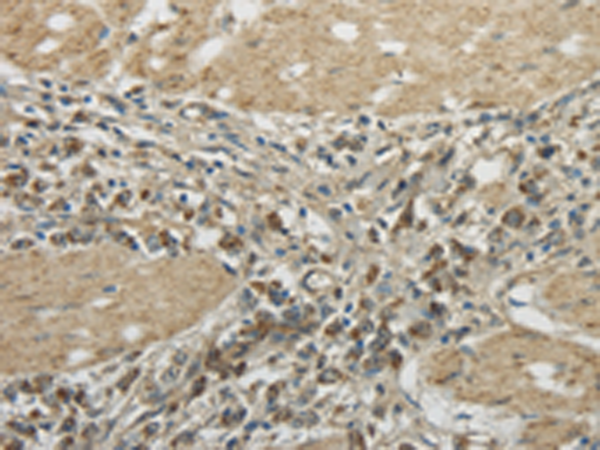

分类: 科研抗体货号: P02040别名: GRNG; HCCA1; HCCA2; YY1AP应用: WB,IHC反应种属: Human, Mouse